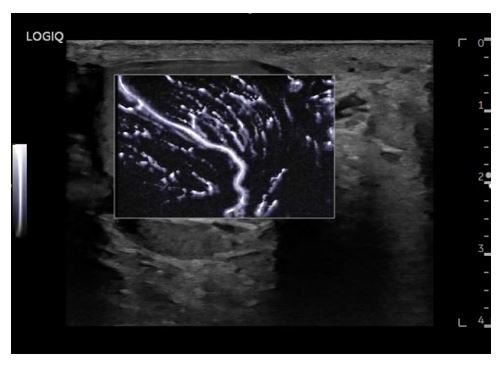

Microvascular Imaging, MVI

마찬가지로 포티스의 기본 옵션으로 파워도플러의 확장형 기능입니다.

높은 속도의 혈류나 연부조직의 노이즈를 제거해서 낮은 속도의 혈류도 감지할 수 있습니다.

미세혈류나 느린 정맥 혈류를 감지하는 기능입니다.